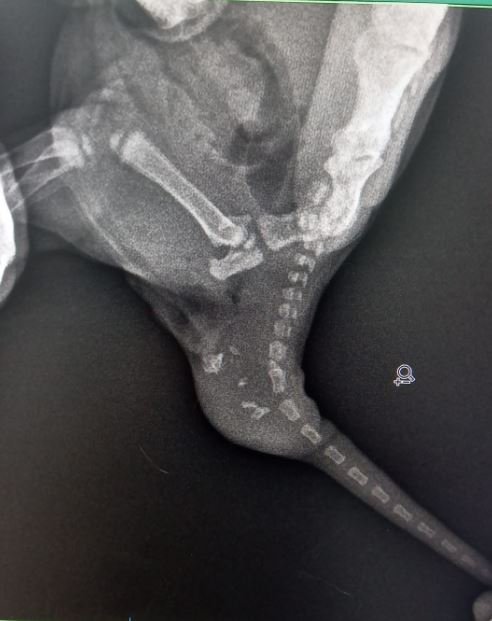

Büşra Nur Yıldız'ın siyam cinsi kedisi, yaklaşık 4 ay önce doğum yaptı. Doğan 2 yavru kediden birinin kuyruğunda şişlik olduğunu fark eden Yıldız, veterinere başvurdu. Veterinerde yapılan kontrolde kedinin kuyruğunda; dişleri, tüyleri, iskelet sistemi, kanal hücreleri oluşan yavru taşıdığı ortaya çıktı. Yavru kediye "teratom" (canavar tümör) tanısı konuldu. Kedi cerrahi operasyona alınarak, tümör temizlendi. Şu an 4 aylık olan kedi, sağlığına kavuştu.

Ameliyatı gerçekleştiren veteriner hekimlerden Emir Düzgören, kedi ile ilgili vaka bildirim raporu hazırlayacaklarını belirterek, "Yavruyu anesteziye uygun hale geldiğinde röntgene aldık ve içeride kemik benzeri dokular olduğu tespit edildi. Ardından çocuğun kuyruğunun alt bölümüne teratom tanısı konuldu. Çoğalan hücrelerden birinin bir tümör hücresine dönüşmesi sonucu oluşmuş. Bu çocukta hem deri, kıl, kemik, kanal hücrelerinin tamamı gelişen canavar tümör oluşmuş. Kardeşi gibi düşünebiliriz; ama tıbbi olarak aslında bir tümör. Bilinen tek vaka bildirimi bizim dışımızda yurt dışında var. Vaka bildirim raporu hazırlayacağız, bunu bilimsel dergilere göndereceğiz. İkinci vakanın da gerçekleştiğini dünyadaki tüm veteriner camiası bilecek. Operasyon çok başarılı geçti. Diğer kardeşi ile aynı, operasyon izi dahi kalmadı. Çok heyecanlandık. Muhtemelen meslek hayatımızda bir daha böyle bir vakaya denk gelmeyeceğiz. Belki Türkiye'de bile bir daha böyle bir vaka olmayacak. Bize denk geldi" dedi.